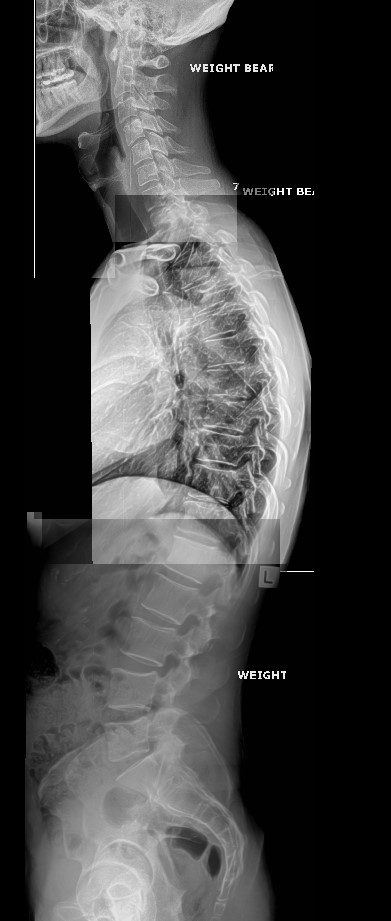

Full spine spinal x-rays